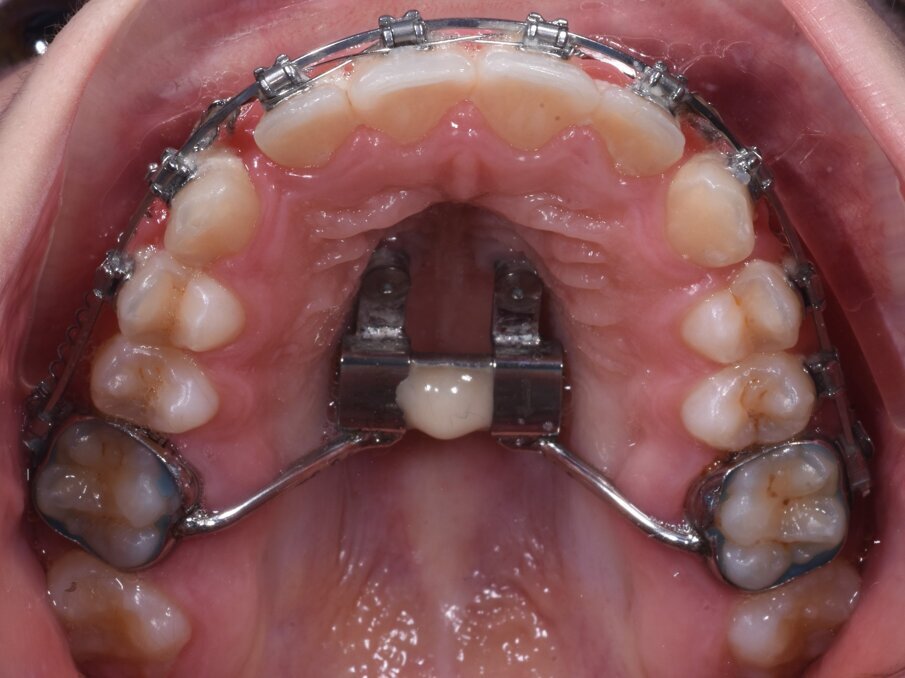

In questo stadio la fusione della sutura è già avvenuta parzialmente o totalmente, ed è quindi stata eseguito una MARPE. È stata progettata una dima CAD/CAM, mediante protocollo Easy Driver5. La CBCT è stata sovrapposta alla scansione digitale STL (standard triangulation language) dell’arcata dentale superiore, per valutare con estrema precisione il sito più adatto di inserimento, la lunghezza e il diametro delle viti, rispettando la profondità della volta palatina, e l’inclinazione di inserimento delle viti (Fig. 4).

È stata quindi prodotta una dima guida, prodotta con la tecnica additive manufacturing. La dima contiene tutte le informazioni programmate digitalmente per l’inserimento di 2 miniviti BENEfit di 9 mm di lunghezza e 2 mm di diametro. In un’unica seduta sono state posizionate TADs ed espansore palatale ibrido. Il protocollo di attivazioni eseguito ha previsto 5 attivazioni al momento dell’inserimento dell’apparecchiatura, e successivamente 1 attivazione al giorno per 20 giorni. Una volta corretta la trasversalità, il caso è stato finalizzato mediante terapia ortodontica con brackets su entrambe le arcate. Le miniviti e l’espansore rapido palatale sono rimaste in sede per tutta la durata della terapia ortodontica, di circa 20 mesi (Figg. 5a-5d). L’espansione scheletrica mascellare ottenuta è stata di 5,6 mm, evitando compensi dentali sui primi molari (Figg. 6a, 6b).

Fig. 5a_Inserimento miniviti.

Fig. 5b_Applicazione in un’unica seduta di espansore palatale ibrido ad appoggio dentale e scheletrico.